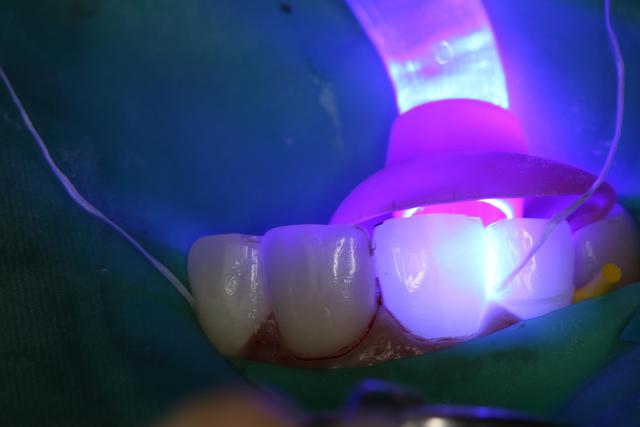

J'ai posé un autre cas d'Emax avant hier pas trop mal, patient content.

Sur 21 très large sur laquelle j'ai fait apexification au MTA.

Variolink II teinte A3